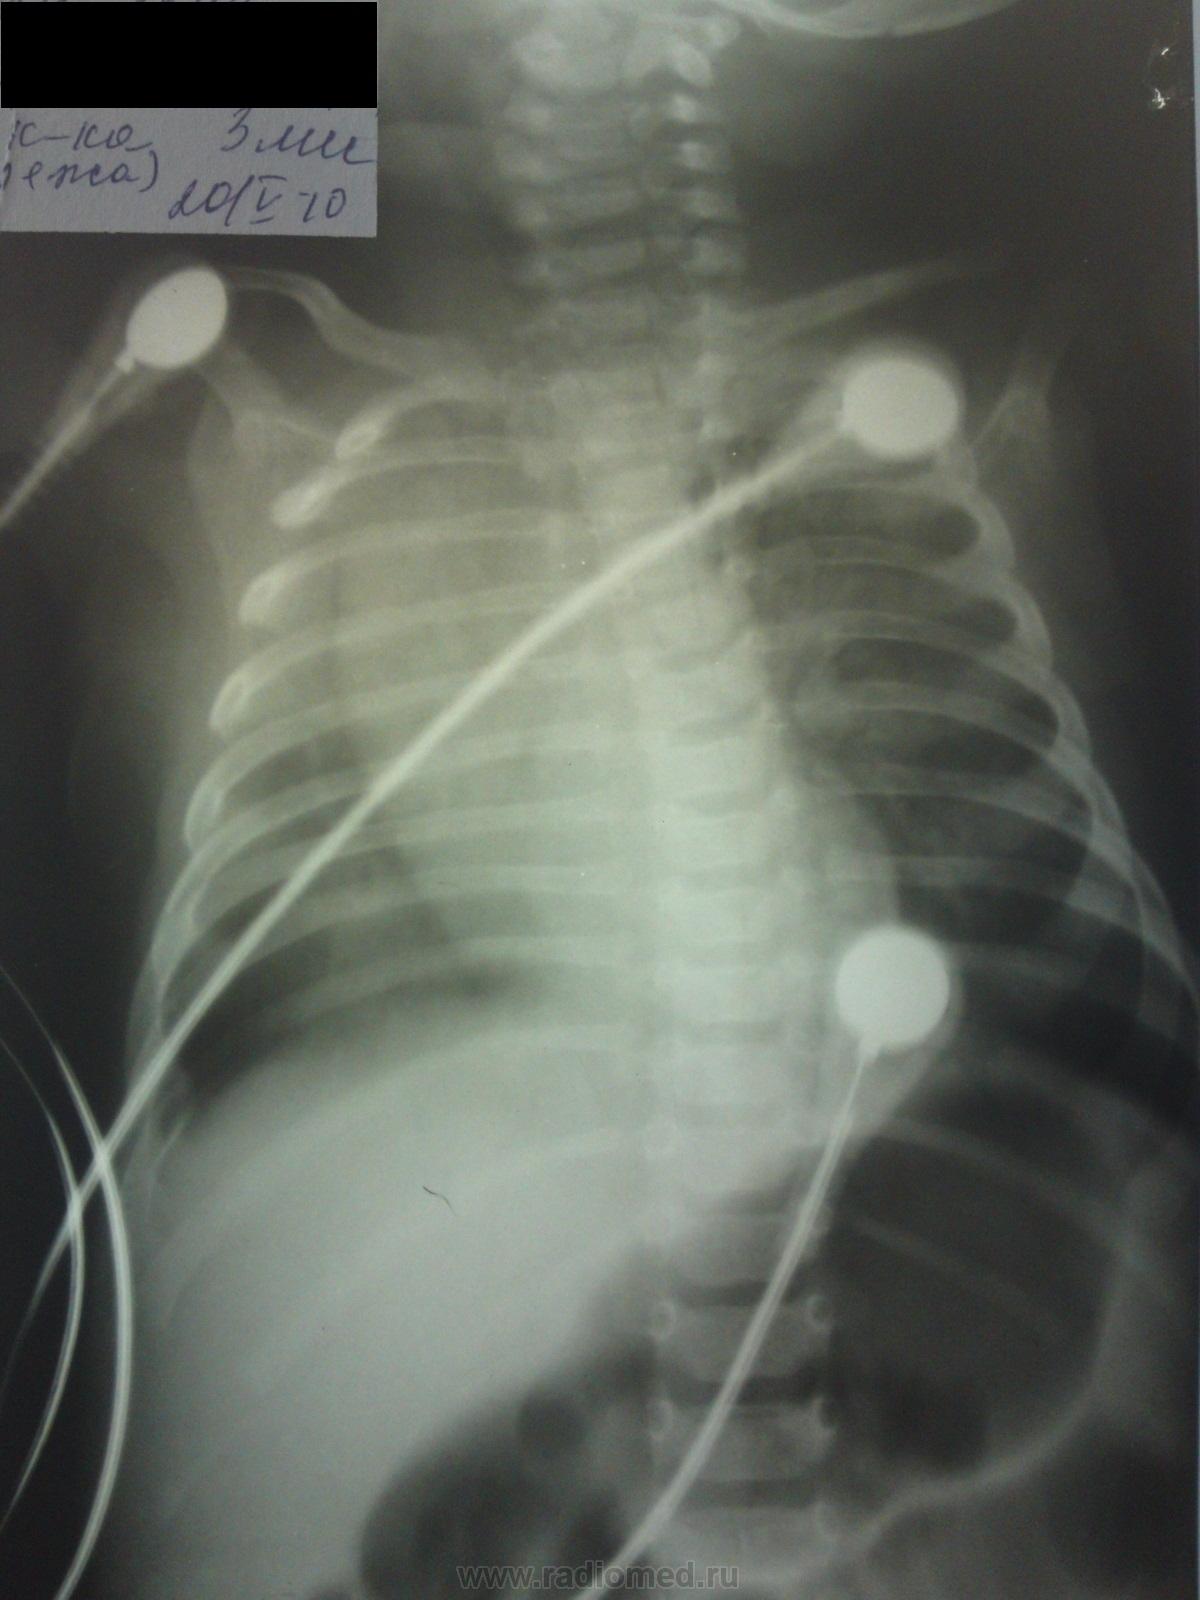

Из анамнеза: Отец покормил ребенка около 3 часов ночи и с матерью вышел из комнаты. Со слов, отсутствовали минут 5. По возвращении увидели, что старший ребенок (2 года) лежит животом на лице младшего. Когда его сняли, то увидели, что у младшего из носа пенистые выделения с примесью крови, лицо синюшного цвета, дыхание отсутствует. Отец начал сам делать сердечно-легочную реанимацию. Сначала были судорожные вдохи, а затем восстановилось спонтанное дыхание. Вызвали "03". Госпитализирован в ОАР. Предварительные диагноз: механическая асфиксия. При поступлении тахикардия 200 и выше, тахипноэ до 70 и выше, гепатомегалия. Ребенок в тяжелом состоянии. На момент осомтра в сознании. Кожа чистая, цианоза нет. Дыхание частое, поверхностное, с легким втяжением межреберных промежутков. Дыхание проводится по передним полям, в верхних отделах - бронхофония. Хрипы не выслушиваются. Неврологичесой симптоматики нет. В ОАК лейкоцитов 16 тысяч, СОЭ 4, без сдвига формулы, в ОАМ глюкозурия. УЗИ ОБП и плевральных полостей без особенностей. В 4:20 произведена рентгенография ОГК в прямой проекции в положении лежа палатным аппаратом Siemens Polymobil 10.

Через 4 часа сделана контрольная рентгенография в прямой и правой боковой проекции в тех же условиях и положении больного.

Вопросы возникли следующие: наличие гиповентиляции (ателектазов)? Наличие пневмоторакса (в т.ч. спонтанного)? Наличие перелома переднего отрезка VIII ребра справа (хотя сам лично я не вижу даже подозрений на перелом)?

На повторной рентгенограмме в прямой проекции смущает наличие линейной тени от уровня заднего отрезка  VI ребра к косто-диафрагмальному синусу.

Справа пневмоторакс, без напряжения, травматический - после реанимации, теоретически должен быть перелом ребра, но достоверно не видно...

Пневмоторакс по латеральной стенке? Или в области синуса? Дело в том, что в области синуса по моему мнению просматривается все-таки легочный рисунок, но смазанный в результате динамической нерезкости.

К тому же я сомневаюсь, что человек делавший СЛР (отец ребенка) делал по правилам... Просто пару толчков в область сердца, то есть слева, но никак не правые, нижние отделы. А что со смещением срединной тени (хоть снимок и выполнен с разворотом, все-таки оно имеет место быть)?

Репродукции рентгенограмм нагоняют тоску. Хочется верить, что подлинники были лучшего качества. Пневмоторакс, если и есть, небольшого объёма и погоды не делает, а вот срединная тень, даже с учётом поворота, как-то настораживает. Хотелось бы увидеть кристально-ясное мнение любимых детских рентгенологов, но сегодня уж поздно наверное…

Есть перелом бокового отдела 8-го ребра справа, пристеночный пневмоторакс, срединная тень расширена за счет тимуса, смещена вправо, не исключено, что за счет ателектаза (или гиповентиляции) верхней доли правого легкого - выраженное и стойкое смещение

Динамика положительная лишь в том, что разрешился ателектаз. Справа, думаю, сейчас есть пневмония. А по первым снимкам - ребенок, конечно, сильно развернут, но даже для такого разворота очень выраженное смещение срединной тени, значит, был ателектаз. На счет пневмоторакса - не знаю, сложно сказать был или нет, я бы на тот момент сделала прямую рентгенограмму, но на левом боку, чтоб четко отдифференцировать, пневмоторакс это или нет. Кстати, перелом ребер совсем не обязателен, чтоб возник пневмоторакс у новорожденного. По поводу срединной тени - это вилочковая железа.